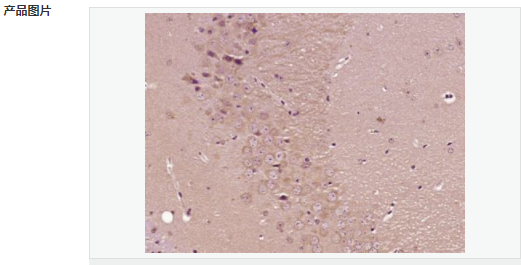

交叉反應(yīng):Mouse,Rat(predicted:Human,Pig) 推薦應(yīng)用:IHC-P,IHC-F,IF,ELISA

| 產(chǎn)品應(yīng)用 | ELISA=1:5000-10000 IHC-P=1:100-500 IHC-F=1:100-500 IF=1:100-500 (石蠟切片需做抗原修復(fù)) not yet tested in other applications. optimal dilutions/concentrations should be determined by the end user. |